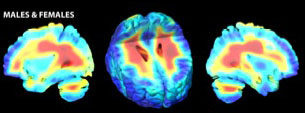

Childhood onset schizophrenia patients

Healthy Controls

Average rates of white matter tissue growth (red) and tissue loss (blue) for healthy controls and childhood onset schizophrenia (COS) patients. COS patients' brains developed an asymmetrical pattern, with white matter growing at up to a 2.2 percent slower-than-normal yearly rate in the right hemisphere. 3-D tensor based morphometry MRI maps created from MRI scans of 12 patients and 12 matched controls over a 5-year period.